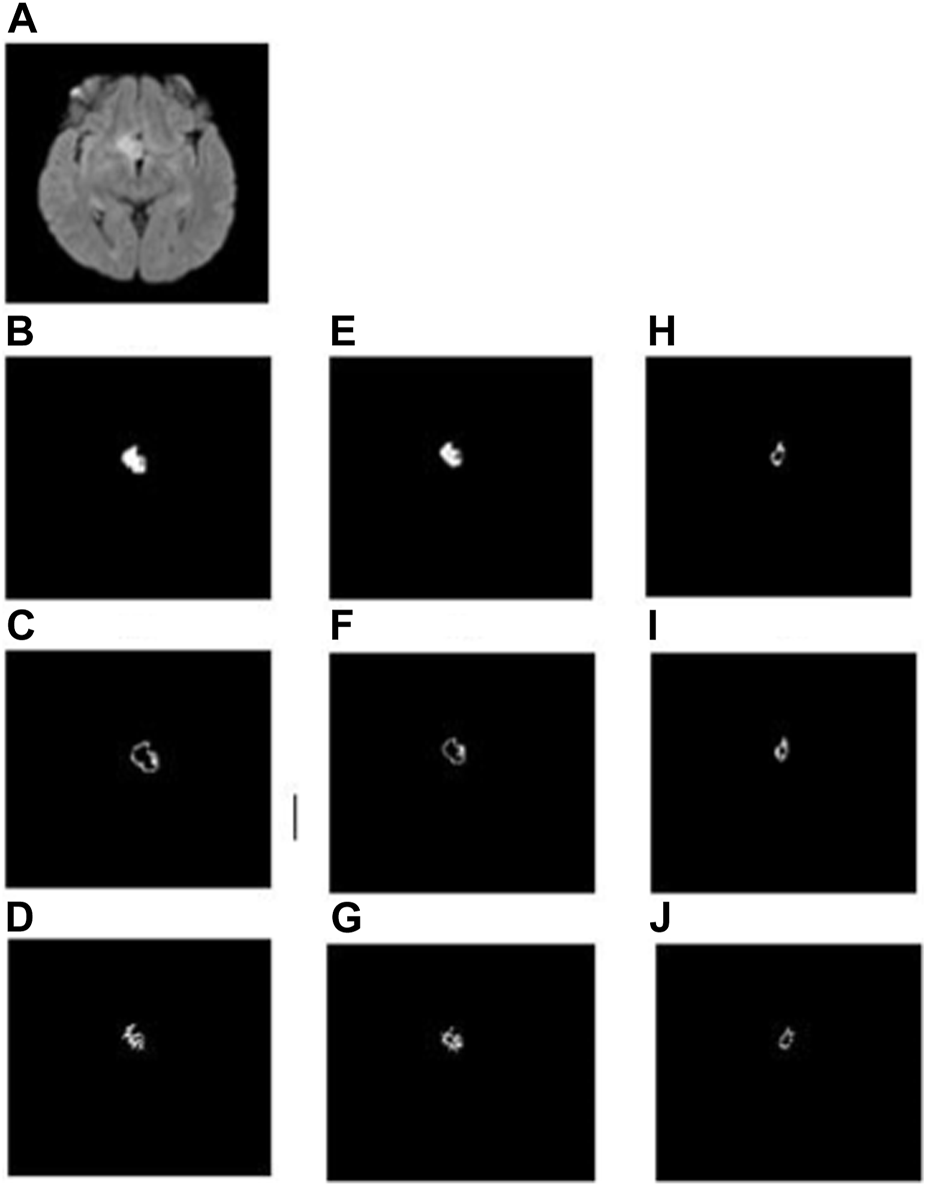

In the whole tumor general structure FD analysis, the boxes which covered the entire tumor region were considered while estimating the FD values. For the boundary FD structure analysis, the voxels within the tumor regions were removed by leaving out only the boundary voxels. This was performed by using the MATLAB morphological operation function “bwmorph.” Then, FD values for the boundary structure were estimated by counting the number of boxes that cover the boundary voxels. Similarly, in the case of skeleton FD analysis, the boundary voxels of the tumor region were removed without changing their general structure. This involves shrinking the input image until the region of interest is 1 pixel wide and equidistant from the image boundaries. The morphological operation was accomplished using “bwmorph,” a built-in MATLAB function. Finally, the FD value was calculated for the skeleton by counting the number of boxes required to cover the skeleton of the tumor region. Figures 2, 3 show the general structure, boundary, and skeleton of a typical LGG and HGG patient. In total, we have nine FD features (three for the whole tumor, three for enhanced tumor, and three for edema, where the three features are general structure, boundary, and skeleton) of the aforementioned tumorous regions.

FIGURE 2

(A) FLAIR image of a typical LGG patient, (B–D) general structure, boundary, and skeleton of the whole tumor region, (E–G) general structure, boundary, and skeleton of the edema region, and (H–J) general structure, boundary, and skeleton of the enhanced tumor region, respectively.

3.2 Fractal dimension analysis of the tumor and its constituents

FD general structure, boundary, and skeleton values measured from the whole tumor, enhanced tumor, and edema regions (i.e., in total, nine FD measures) were compared between LGG and HGG patients. Figures 2, 3 show the different structures of the tumor and its constituents on which FD estimates were performed in a typical LGG and HGG patient. Statistical analysis revealed that the FD skeleton of edema (p = 0.0009), FD skeleton of the enhanced tumor region (p < 0.0001), FD boundary of the whole tumor (p = 0.0105), and FD general structure of the enhanced tumor region (p < 0.0001) were significantly different between LGG and HGG patients. The remaining FD measures did not show any statistical significance in distinguishing the tumor grades. These results, along with mean and standard deviation values of the FD measures, are given in Table 3. In general, FD values were higher in HGG patients than in LGG patients. This is probably due to the irregular tumor structure observed in the MRI of HGG patients.